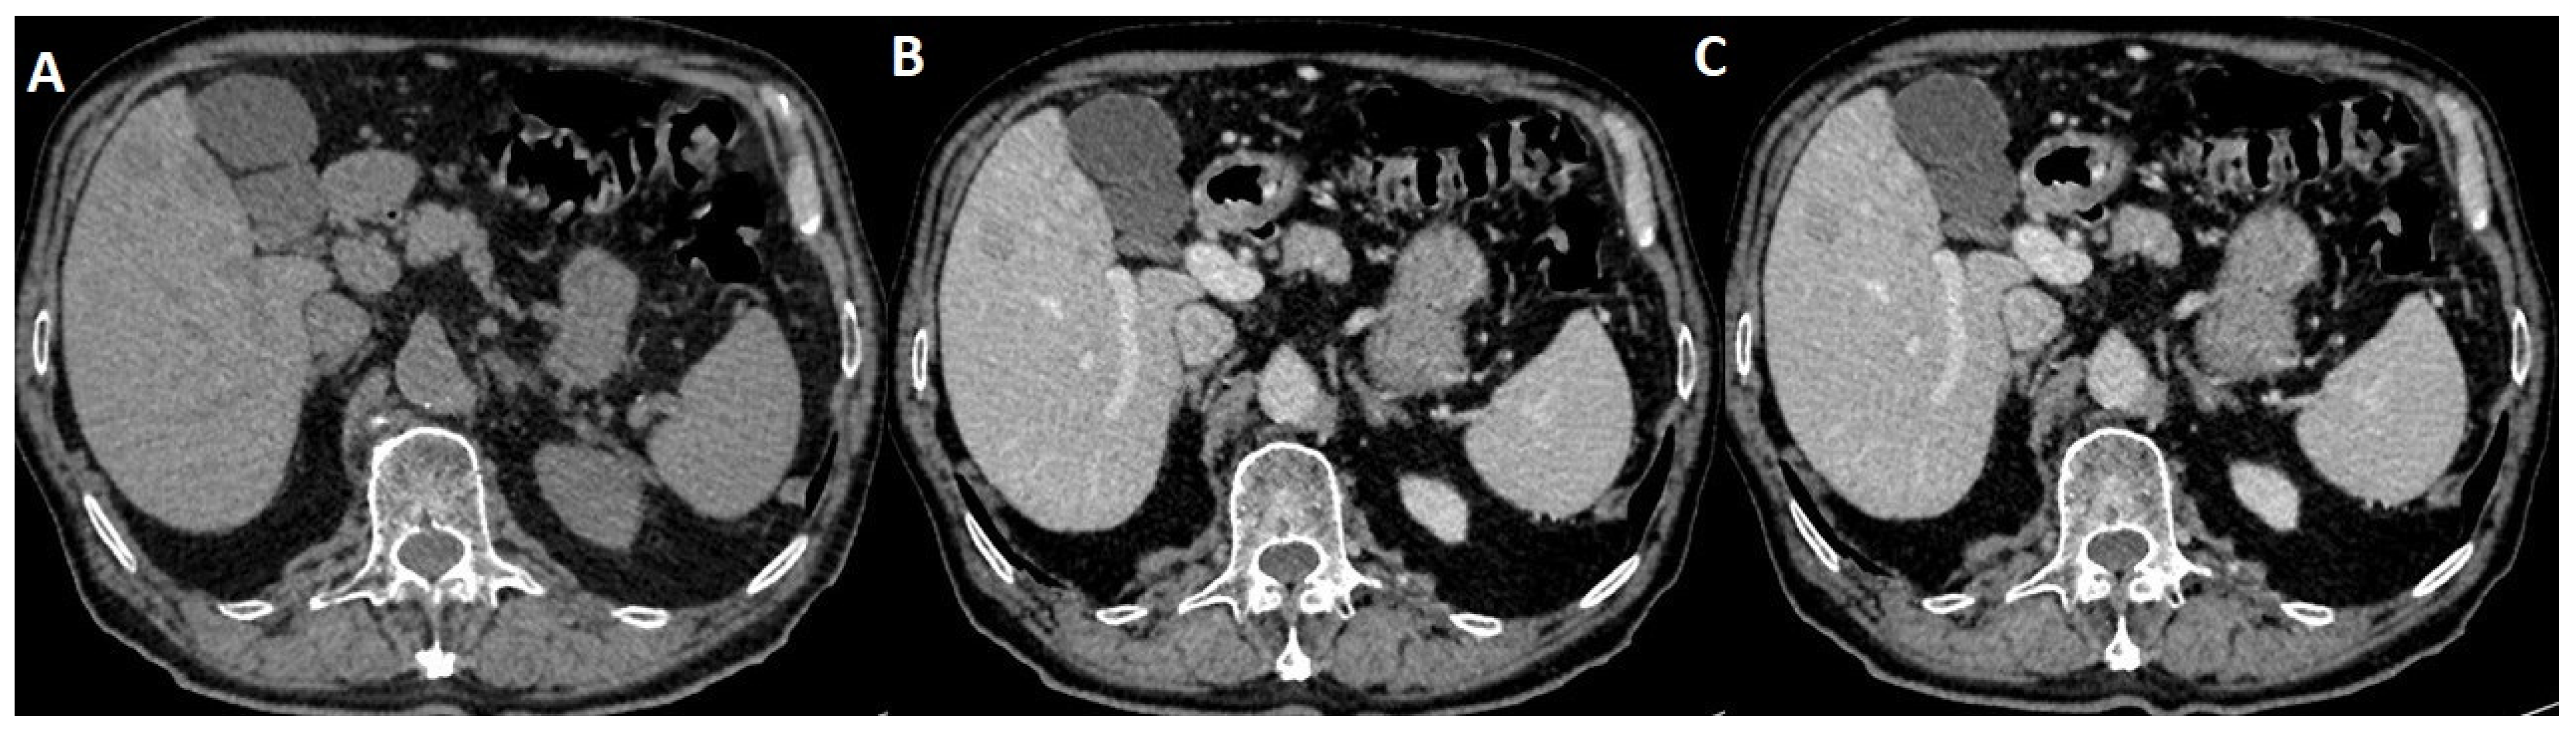

2.3. MRI Dynamic Three-Phasic Scanning

2.4. Delayed Multiphase Scanning